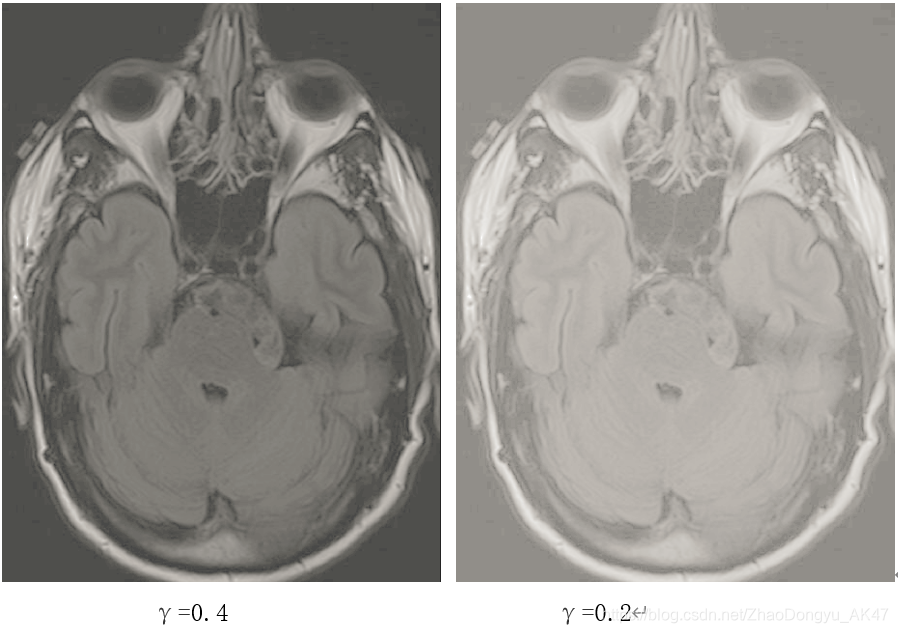

处理结果:

分析:

如幂次变换特点——当γ<1,此时扩展低灰度级,压缩高灰度级,使图像变亮;当γ>1,此时扩展高灰度级,压缩低灰度级,使图像变暗。

感觉在γ为0.4时相比于0.6的一些细节更清晰一些,当γ为0.2时图片有点过亮,一些细节反而不容易观察。

另外,还测试了γ分别为0.1,0.2,0.3,0.4……0.9的结果,发现确实可以通过幂律变换实现亮暗度变化的对比度增强。